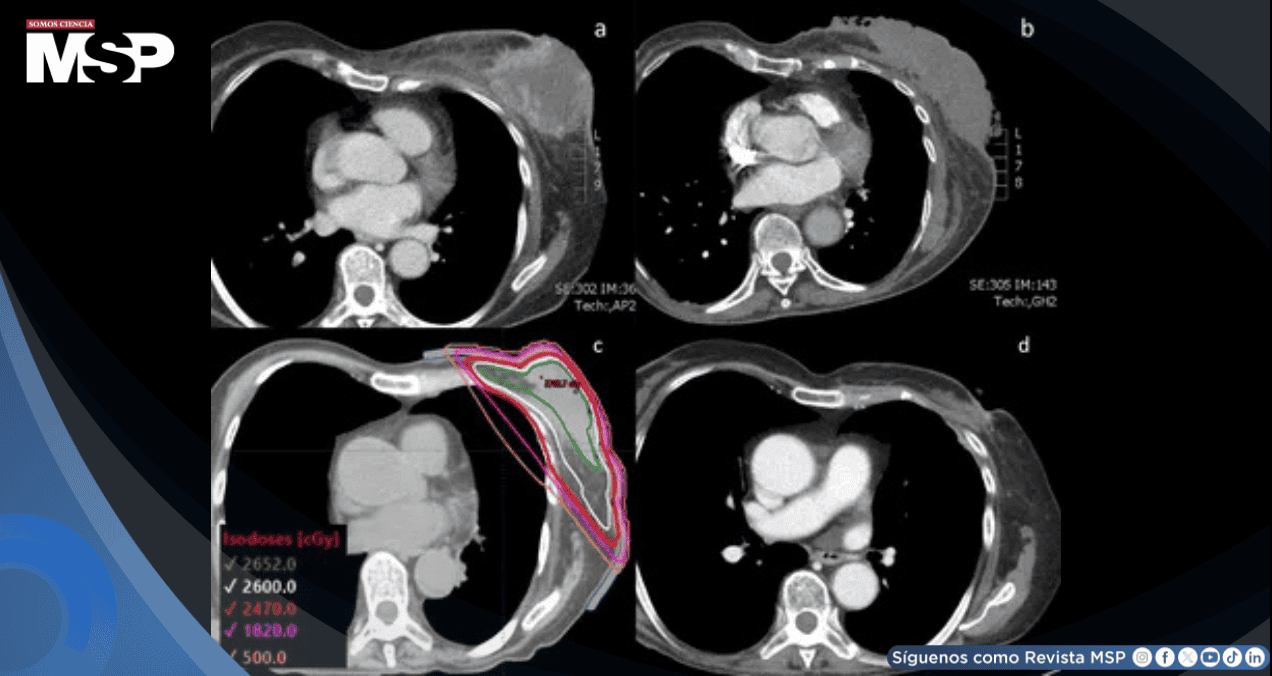

Ante la progresión sintomática se decidió suspender la doxorrubicina e iniciar radioterapia ultrahipofraccionada a toda la mama izquierda con esquema FAST-Forward de 26 Gy en 5 fracciones.

La simulación se realizó en posición supina con brazos elevados sobre tabla de alas, utilizando técnica de retención respiratoria en inspiración profunda con gestión de posición en tiempo real.

El plan tridimensional conformado cubrió toda la mama desde el borde inferior de la clavícula hasta 2 cm por debajo del surco inframamario, desde el esternón medio medialmente hasta la línea axilar media lateralmente.

Se emplearon campos tangenciales con bloques de media viga, energía de 6 MV y bolo de 5 mm sobre la piel. Los parámetros dosimétricos cumplieron con las restricciones del protocolo FAST-Forward: V95% de mama izquierda 98,4%, dosis media cardíaca 0,35 Gy, dosis media a arteria coronaria 0,99 Gy, V8 Gy de pulmón izquierdo 8,42%, V12,5 Gy 6,8%, y dosis máxima 104,7% de la dosis prescrita. Se realizó verificación diaria con imágenes ortogonales de kilovoltaje.

La tomografía de tórax realizada 3,5 meses después de completar la radioterapia ultrahipofraccionada demostró una reducción tumoral dramática, con medidas de la masa de 0,8 x 1,8 cm, representando una respuesta clínica mayor.